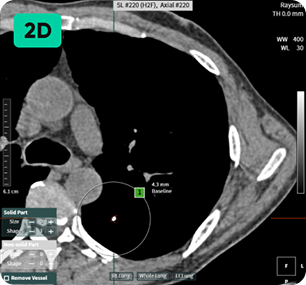

2

후속 모드

후속 조치와 이전 폐 CT 스캔을 자동으로 매칭하여 결절 변화를 즉시 평가합니다.

정확한 판독을 위해서는 결절 성장을 모니터링하는 것이 중요합니다.

aview LCS는 단순한 이미지 비교를 넘어 폐 결절을 매칭하여 성장과 변화를 자율적으로 평가합니다. aview LCS는 미국 영상의학회에서 권장하는 폐 CT 스크리닝 보고 및 데이터 시스템(Lung-RADS ver 1.1) 가이드라인에 따라 폐 결절을 관련 범주로 효율적으로 분류합니다.

후속 CT 스캔

이전 CT 스캔